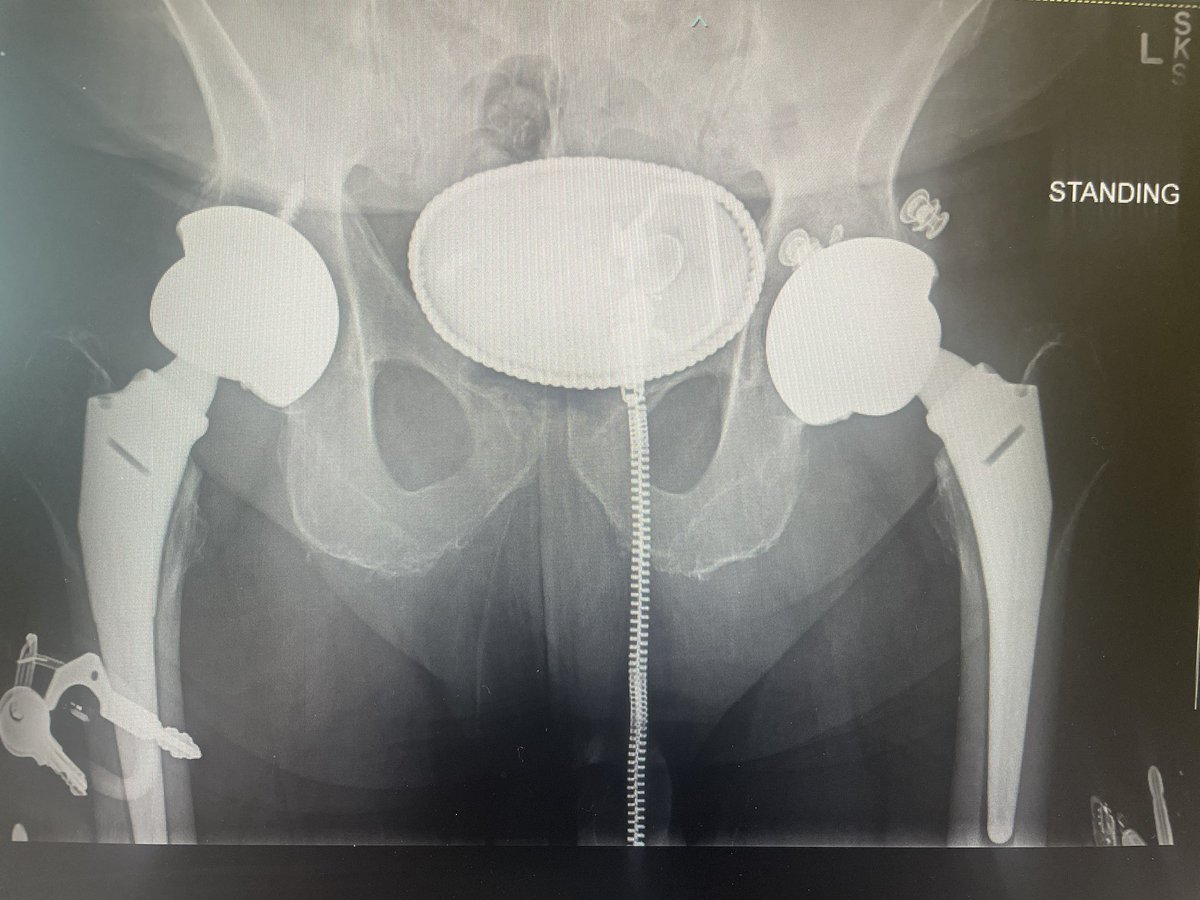

@aschwartz45 @generalorthomd Those are tm modular sockets, not continuum. Will need trilogy liners